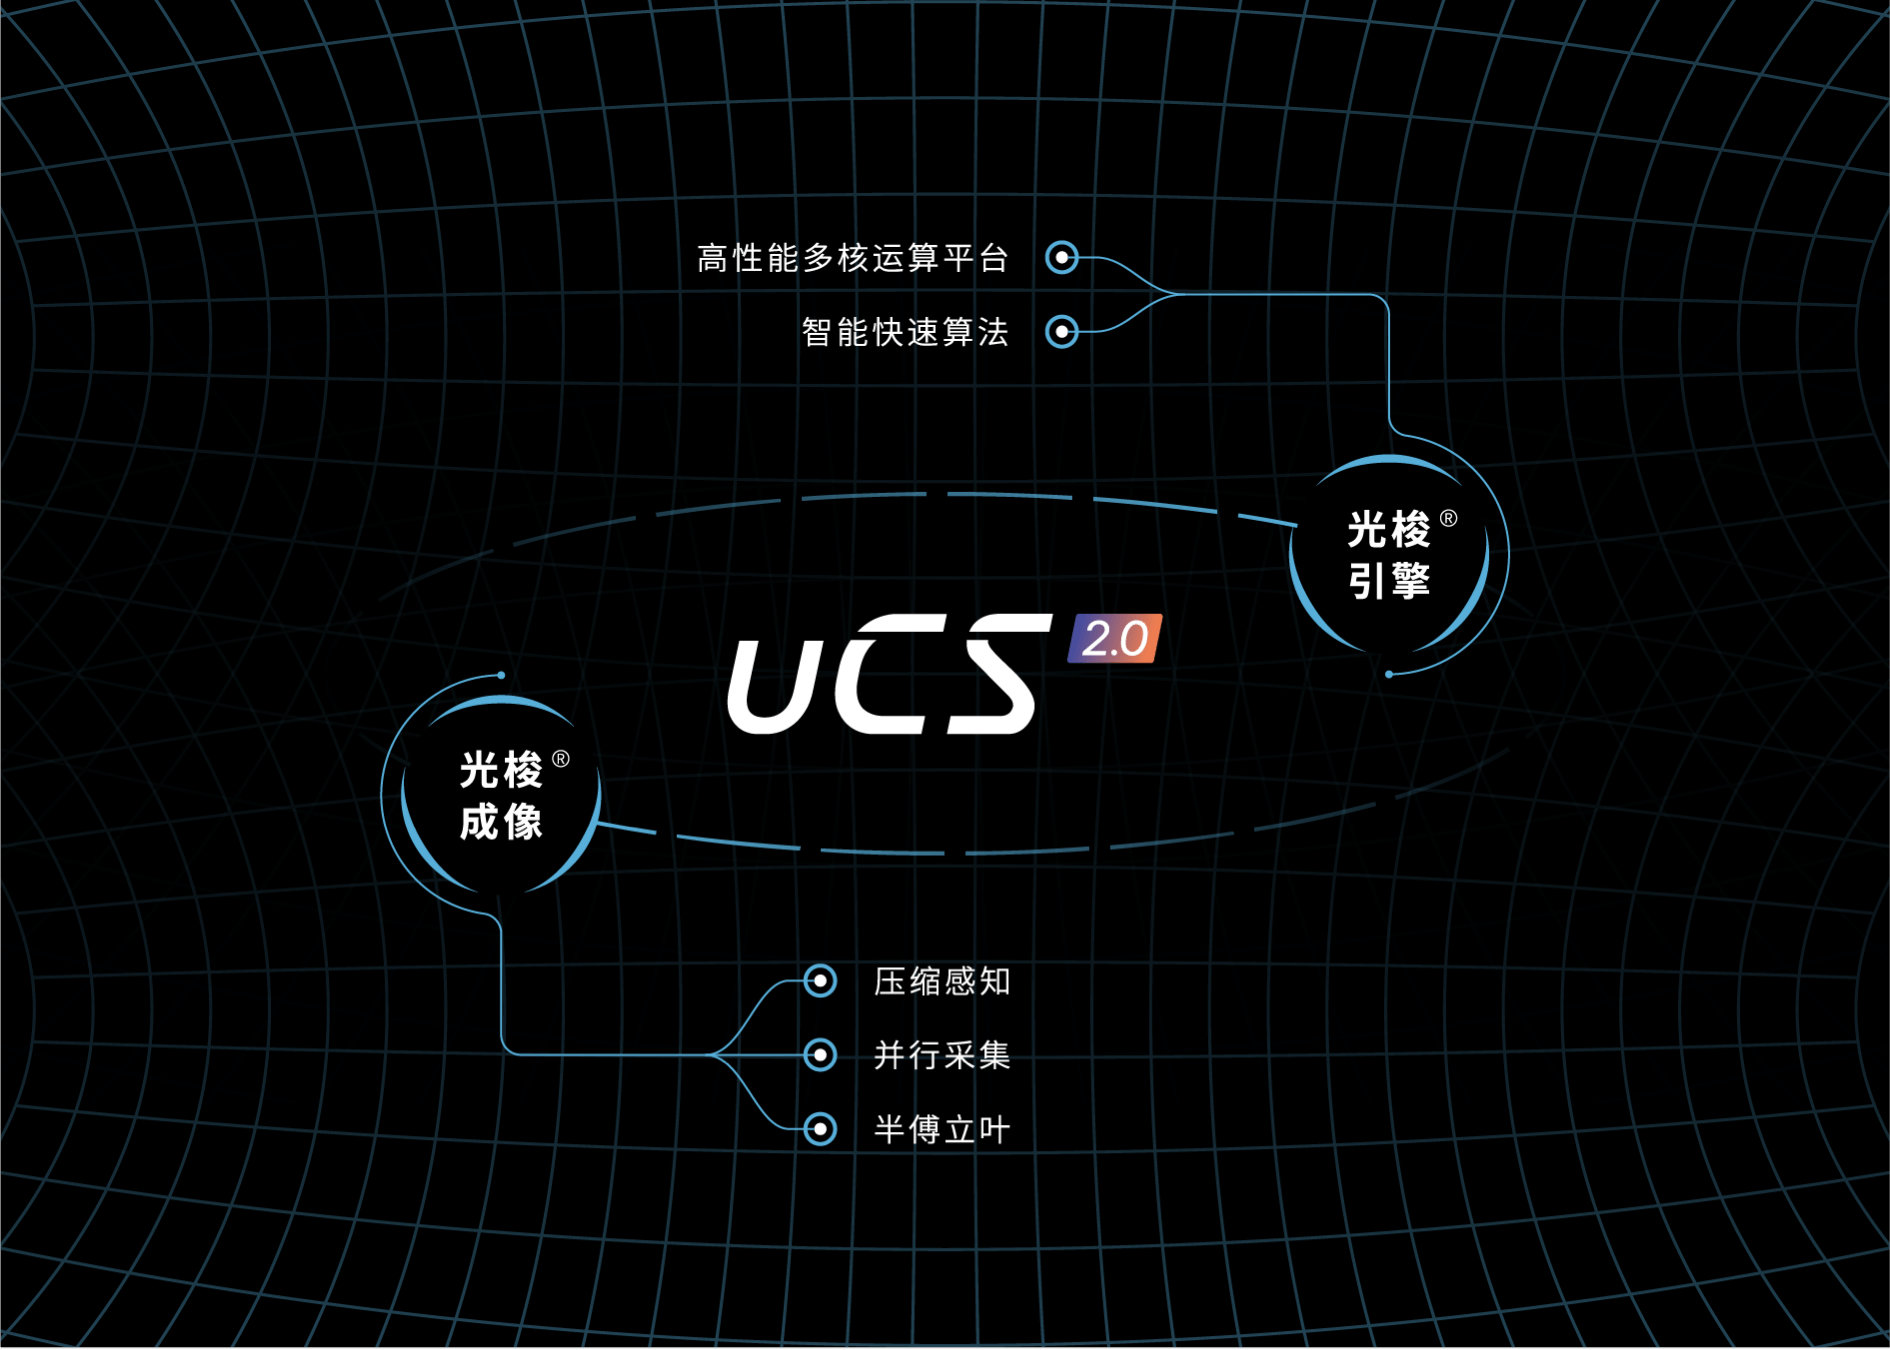

光梭®2.0成像

融合半傅里叶、并行成像以及压缩感知技术,充分挖掘图像加速潜力。

迭代式重建技术,多种技术互相校验,实现更优图像质量和更高加速因子。

光梭引擎采用高性能专用CPU,配备超大内存及高速数据传输网络,配合专为高强度并行计算优化的重建框架,满足实时光梭®成像技术的临床要求。

光梭®2.0成像

融合半傅里叶、并行成像以及压缩感知技术,充分挖掘图像加速潜力。

迭代式重建技术,多种技术互相校验,实现更优图像质量和更高加速因子。

光梭引擎采用高性能专用CPU,配备超大内存及高速数据传输网络,配合专为高强度并行计算优化的重建框架,满足实时光梭®成像技术的临床要求。